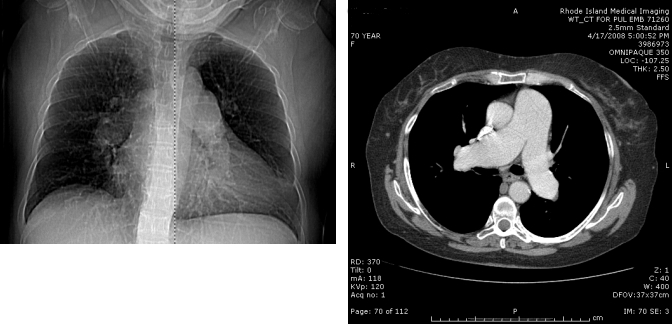

CT chest with contrast:Enlargement of the right and left main pulmonary arteries; no proximal-filling defects. No active lung disease, mild emphysematous changes without bullous emphysema. The liver is cirrhotic with evidence of esophageal and periportal varices (Figure 2).

Figure 2. CT pulmonary angiogram scout film (Left) and axial cut (Right) showing severe dilation of the pulmonary artery trunk and main right and left branches. Note the diameter of the pulmonary artery exceeds that of the aorta. No proximal filling defects are seen.